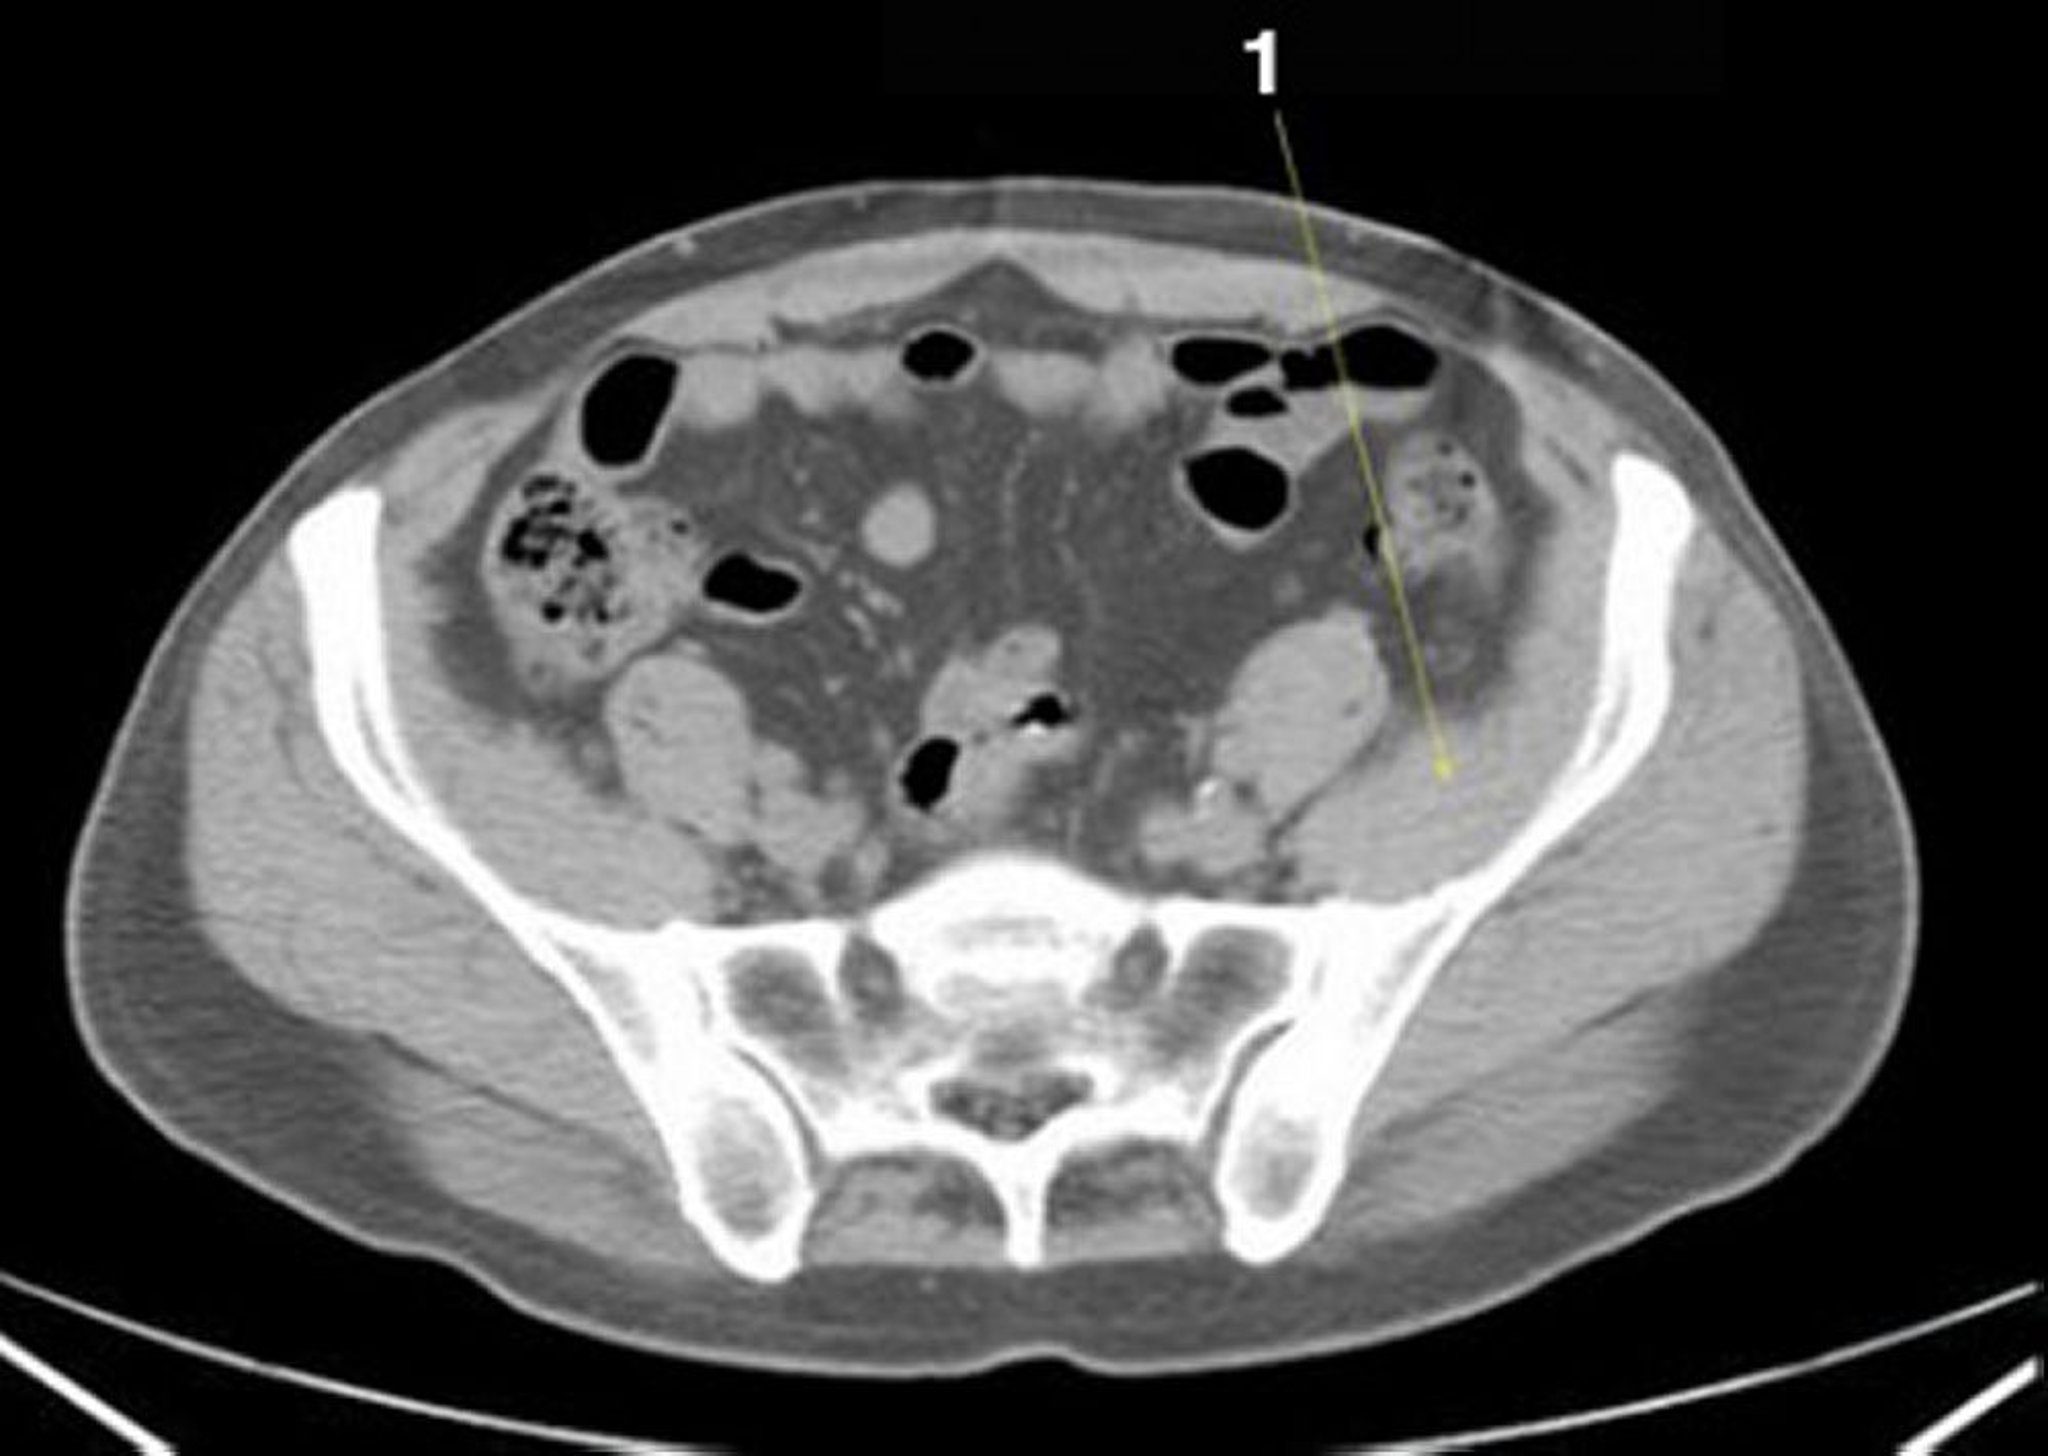

Source: bhstechltx.pages.dev Beurteilung des Gastrointestinalpatienten Gastrointestinale Erkrankungen MSD Manual Profi , Was ist eine CT-Abdomen? Eine Abdomen-CT (Computertomographie des Bauches und Beckens) ist die mittels Röntgenstrahlen erfolgende Untersuchung des Bauchraumes Hier gibt es gewaltige Dichteunterschiede der verschiedenen Gewebe zu berücksichtigen

Source: flexjsosi.pages.dev ImageCTScan von Abdomen und Becken mit normaler Anatomie ohne Kontrastmittel (Folie 19)MSD , CT-Untersuchungen, die normalerweise ohne Kontrastmittel auskommen, sind beispielsweise Kopfuntersuchungen mit der Frage nach einer Blutung, die Frage, ob eine COVID-19-Lungenentzündung vorliegt, die Suche nach einem Harnleiterstein und Beurteilungen von Knochen und Gelenken. Auch Eingriffe wie das Einsetzen von Stents finden oft unter Kontrastmittelgabe statt

Source: neurunign.pages.dev ImageCTScan von Abdomen und Becken mit normaler Anatomie ohne Kontrastmittel (Folie 22)MSD , Erforderliche Services akzeptieren Ohne Einwilligung schließen. Hier gibt es gewaltige Dichteunterschiede der verschiedenen Gewebe zu berücksichtigen